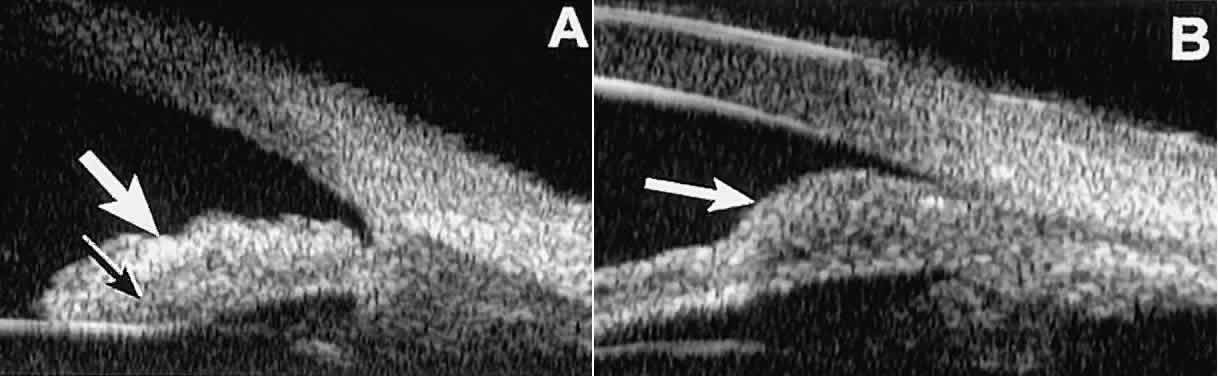

After any type of glaucoma filtering surgery,10 UBM can be used to detect and evaluate the extent of postoperative complications

such as ciliochoroidal effusion and cyclodialysis.3,4 In ciliochoroidal effusion (Fig. 13A), UBM shows the ciliary body to be edematous and separated from the sclera

by a sonolucent collection of supraciliary fluid. Many ciliochoroidal

effusions that are too limited in extent to be detectable by indirect

ophthalmoscopy and slit lamp biomicroscopy can be imaged by UBM. In

cyclodialysis (see Fig. 13B), UBM shows a well-defined separation between the uveal tissue and the

sclera in the region of the scleral spur. The width of the cleft is usually

assessed best by means of limbus-concentric images through the

region of interest.  Fig. 13. Complications of intraocular surgery. A. Postoperative ciliochoroidal effusion appears as slitlike spaces filled

TRAUMA After blunt ocular trauma, UBM can be used to evaluate iris-angle abnormalities

of blood clots.4 Angle recession is characterized on UBM (Fig. 21A) by posterior displacement of the point of attachment of the iris to the

sclera. In the acute stage, the post-traumatic recess is usually filled

with blood. Cyclodialysis (described and illustrated earlier) appears

on radial UBM slices through the limbal region (see Fig. 13B) as a fluid-filled cleft between the sclera and ciliary body.13 This abnormality is by definition associated with at least a localized

ciliochoroidal effusion.  Fig. 21. UBM features of ocular trauma. A. Angle recession with traumatic hyphema after blunt injury. B. Intracorneal foreign body (rose thorn fragment). Note inflammatory cells